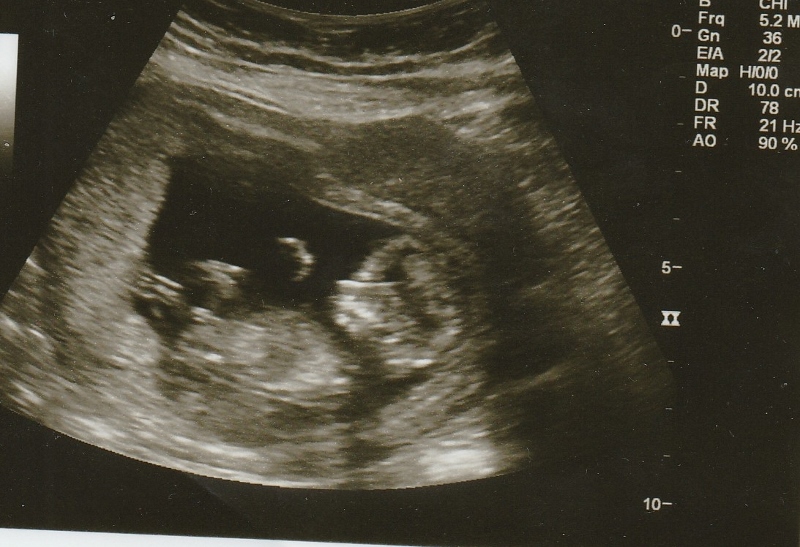

12w3d Nub guess anyone?

Hi! I had my first scan today at 12w3d and baby was measuring just a couple days ahead. Any guesses based on the nub? Thanks!! I am not sure that these all havve a clear nub but thought i'd add them just in case.

I'm newer to nub guessing, but thinking boy. :)

I'm guessing boy

I think its a boy! Good luck!

Thats a screaming boy! Congrats

Im very new at guessing but it is really screaming boy to me! :fx: I'm right this time ;)

I thought I was getting the hang of this nub spotting, but I thought this looked girly, so obviously I'm looking at the wrong spot on the picture. If anyone can circle the part of the pictures that shows the boy nub, I would really appreciate it

I think I know why you went girly Christi. Look at the second picture that is the most obvious boy one. The rest show a stacked split nub at a high angle. Fork only means girl if its still level and not stacking.